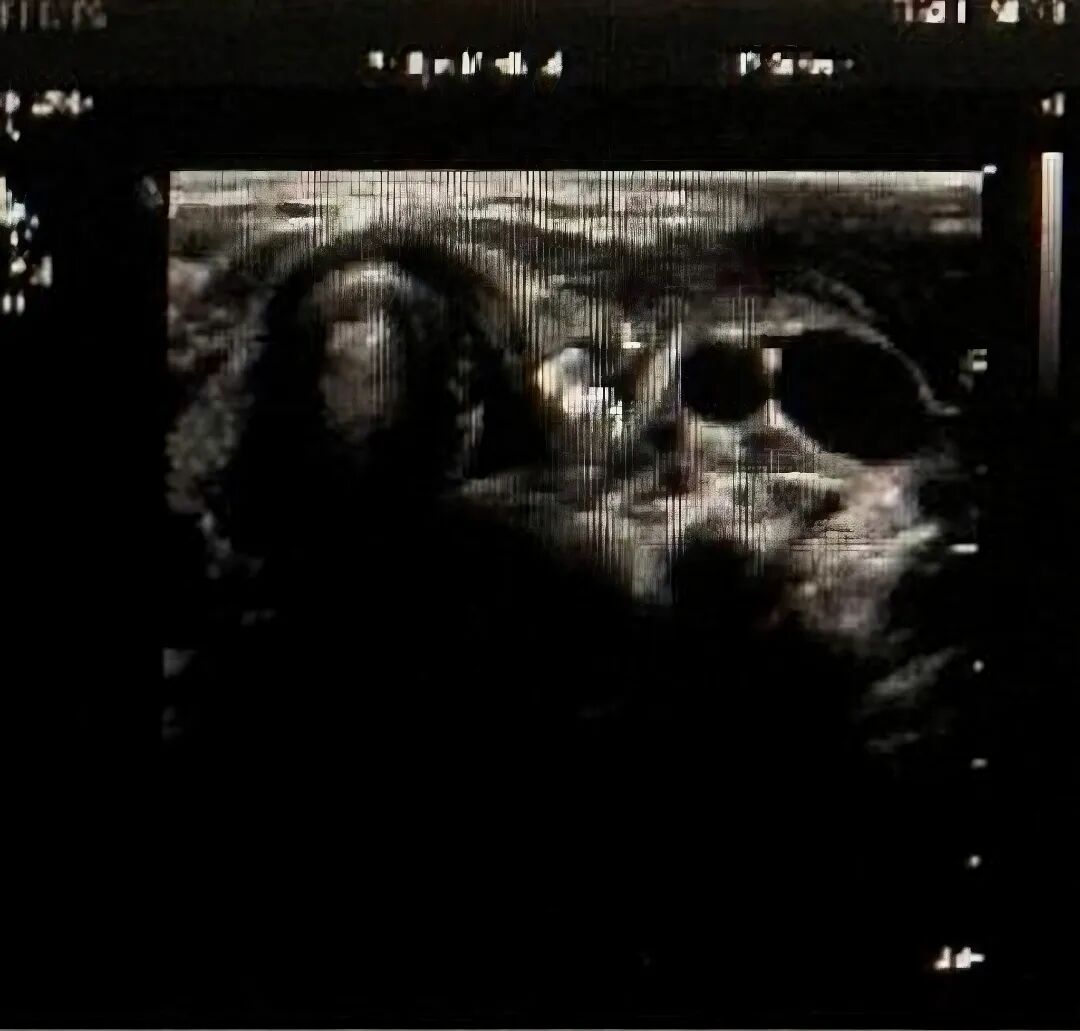

图4:B超下的“异常信号”图

B超检查——“初筛利器”:颈部超声检查,无创、便捷。可以初步评估颈部是否有脓肿形成、脓肿的液化情况,发现瘘管的大致走行方向等,特别是能评估脓肿与甲状腺的关系——这是鉴别梨状窝瘘的重要参考指标!